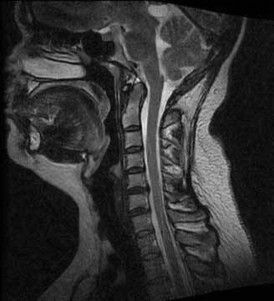

Question 16:

A 52-year-old man presents with sharp neck pain radiating down his right arm. Physical examination reveals weakness in active elbow extension and wrist flexion. He also reports decreased sensation isolated to the dorsum of his middle finger. Which cervical nerve root is most likely compressed?

Correct Answer: C7

Explanation:

Compression of the C7 nerve root causes a classic radiculopathy characterized by weakness in elbow extension (triceps) and wrist flexion (flexor carpi radialis), an absent or diminished triceps reflex, and sensory changes involving the middle finger. C6 radiculopathy typically involves wrist extension weakness and numbness in the thumb and index finger. C8 involves finger flexion and numbness in the small finger.